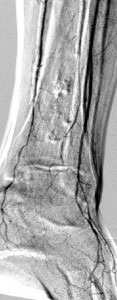

Key to images:

Top panel: Pre-intervention run-off angiogram of the left lower extremity showing, from left to right, irregular left common femoral artery (LCFA) arrowed on the 1st image, absent left superfical femoral artery (LSFA) or any bypass conduit on the 2nd image, sketchy descending collaterals from the left deep femoral (LDFA) that reconstitute a faint shadow of the left popliteal artery, arrowed on the 3rd image. The last 2 images faintly show three-vessel run-off below the left knee. The anterior tibial artery is most opacified, followed by the posterior tibial artery; the peroneal artery peeps through the upper edge of the last image. Note how weakly visible these vessels are due to the poor inflow from above.